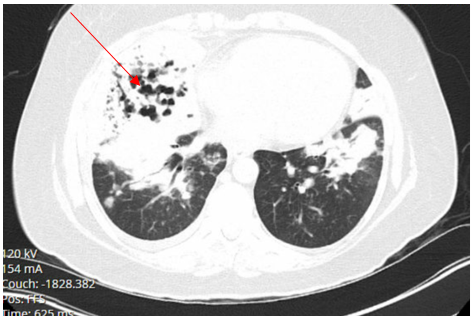

The patient was diagnosed with pulmonary blastomycosis and started on Amphotericin -B 5 mg/kg/ IV every 24 hours, with close monitoring of renal function and electrolytes, including potassium, magnesium, and phosphate. All other Antibiotics and steroids were discontinued. Follow up Chest-X ray a week after bronchoscopy while the patient was in hospital showed extensive bilateral airspace infiltrates in both lungs most pronounced at the bases and CT chest showed progressive consolidations in the right lower lobe, lingula, left lower lobe, and right middle lobe with cavitary appearance in the right middle lobe suggesting necrotizing pneumonia with tiny left and small right pleural effusion (Figures 9 and 10).

Figure 10. CT chest showing bilateral consolidation of the lung bases involving the lingula, left lower lobe, right lower lobe and right middle lobe with cavitary appearance of the right middle lobe consolidation.